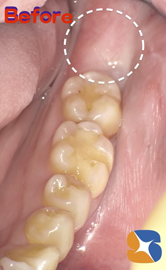

矯正前のお口の状態。いち早く矯正を始めるため、抜歯を急がれていることも納得できます。